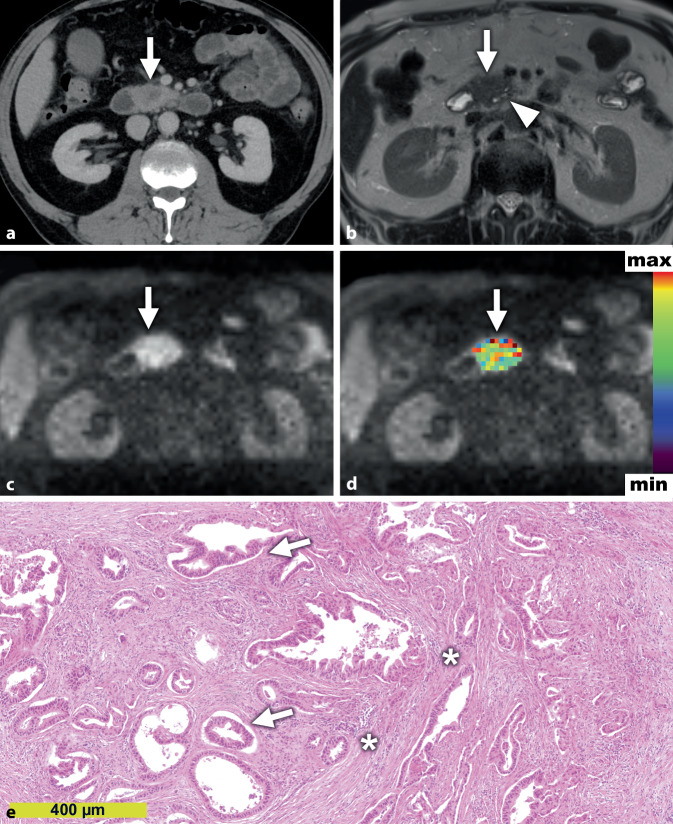

Die meisten PDAC erscheinen radiologisch als unscharf begrenzte minderkontrastierte solide Raumforderungen mit infiltrativem Ausbreitungsmuster. Die kontrastmittelgestützte Computertomographie (CT) und Magnetresonanztomographie (MRT) können mit hoher Genauigkeit PDACs diagnostizieren [27]. Während die MRT aufgrund ihres besseren Weichteilkontrastes Vorteile bei der Detektion von Lebermetastasen hat, ist die CT die meistangewandte und bestvalidierte radiologische Methode zur Beurteilung der Ausdehnung, des Gefäßbezuges und damit der Resektabilität [21, 31]. Auch die extrapankreatische perineurale Invasion lässt sich mit der CT gut vorhersagen [12]. Neben dieser Darstellung der makroskopischen Tumorausdehnung vermögen moderne funktionelle Bildgebungstechniken Mikrostrukturparameter der abgebildeten Gewebe abzuschätzen (Abb. 1), wenngleich die direkte In-vivo-Darstellung einzelner Tumorzellen oder Bestandteile des Stromas mittels nichtinvasiver CT- und MRT-Bildgebung (noch) nicht möglich ist und bisher einzig der mikroskopischen Diagnostik durch den Pathologen vorbehalten ist. Eine gut charakterisierte funktionelle radiologische Untersuchungsmethode ist die kontrastmittelgestützte CT-Perfusion, die zur quantitativen Bestimmung der Gewebedurchblutung verwendet wird. Die CT-Perfusion kann die Detektionsrate von PDACs im CT zu verbessern, da sich das Pankreaskarzinom aufgrund seiner geringen Perfusion als minderdurchblutetes Areal abzeichnet [15]. Eine weitere etablierte funktionelle radiologische Untersuchungsmethode, die diffusionsgewichtete MRT (DW-MRT), kommt ohne Kontrastmittelapplikation und Röntgenstrahlung aus. Die DW-MRT quantifiziert die wärmeinduzierte Bewegung von Wassermolekülen in menschlichen Geweben. Die Diffusion wird klinisch meist durch den sog. apparenten Diffusionskoeffizienten (ADC) quantifiziert, dessen Berechnung ein monoexponentielles Diffusionsmodell zugrunde liegt. Sie ist meist stärker eingeschränkt in kompakten Geweben, die viele mikrostrukturelle Hindernisse (z. B. Zellmembranen bei erhöhter Zelldichte) für die freie Wasserdiffusion aufweisen. Hierzu zählen auch die meisten malignen Tumoren [2]. Auch in den meisten PDACs ist die Diffusion stärker eingeschränkt als im nichtneoplastischen Pankreasparenchym, was zur Detektion der Tumoren nützlich sein kann [2]. Ein Nachteil des monoexponentiellen Diffusionsmodelles ist, dass die ermittelten ADC-Werte auch durch Perfusionseffekte im Gewebe beeinflusst werden. Le Bihan entwickelte daher das biexponentielle Intravoxel-Incoherent-Motion(IVIM)-DW-MRT-Modell, welches eine Trennung von Diffusions- und Perfusionseffekten ermöglicht [2].

Das Pankreaskarzinom erscheint am Operationspräparat makroskopisch in der Regel als derber, solider, unscharf begrenzter Tumor, was oftmals schon rein bildmorphologisch mit den Befunden der CT oder MRT korreliert. Mikroskopisch ist das PDAC aufgebaut aus atypisch konfigurierten Drüsen, umgeben von einem desmoplastischen Stroma, welches den Großteil des Tumorvolumens einnehmen kann [4]. Neben dem prädominanten drüsigen Wachstum, sind auch (mikro-)papilläre, solide-nestartige, kribriforme oder einzelzellig-dissoziierte Muster nachweisbar [19]. Verschiedene Faktoren, wie beispielsweise ein mesenchymaler Tumorphänotyp, sind mit einem einzelzellig-dissoziierten bzw. histologisch schlecht differenzierten Tumorwachstumsmuster assoziiert [7]. Im Gegensatz zur lobulären Anordnung der Drüsen im gesunden Pankreas sind die Tumordrüsen diffus im Stroma angeordnet, deformiert und weisen unvollständige Lumina auf bzw. die Zellen vereinzeln sich [25]. Typisch ist ein dispergiertes Wachstumsmuster, d. h., die Tumorzellen wachsen häufig nicht als zusammenhängende Tumormasse, sondern man findet Zellcluster, die einen erheblichen Abstand zur Haupttumormasse aufweisen und umliegendes Gewebe, Nervenscheiden und Gefäße infiltrieren [29]. Als charakteristisch für das PDAC gilt eine inter- und intratumorale Heterogenität hinsichtlich des Wachstumsmusters, der zytologischen Charakteristika und der Stromaeigenschaften. Zytogenetische Heterogenität wurde sogar zwischen unmittelbar aneinander grenzenden Tumordrüsen berichtet [29]. Das histologische Wachstumsmuster beeinflusst die radiologische Darstellung in der MRT entscheidend. PDAC mit primär glandulärem Wachstumsmuster weisen höhere ADC-Werte auf als solide, einzelzellig oder mikropapillär wachsende PDACs [19]. Zu erklären ist diese Beobachtung damit, dass luminale Strukturen eine freiere Wasserdiffusion ermöglichen verglichen mit soliden Zellverbänden oder gar einzelliegenden Tumorzellen, wo es kaum oder keine freien Lumina gibt. Hierdurch wird das Gewebe deutlich kompakter und somit schränken diese mikrostrukturellen Hindernisse die freie Wasserdiffusion ein.

Der Stromagehalt ist neben der Zelldichte [10] und dem Wachstumsmuster [19] einer derjenigen Mikrostrukturparameter, die maßgeblich die Diffusion in der DW-MRT des PDAC beeinflussen [23]. Die Makromoleküle der EZM stellen physikalische Barrieren für die freie Diffusion von Wassermolekülen dar, weshalb die Diffusion in stromareichen PDACs stärker eingeschränkt ist als in stromaarmen PDACs (Abb. 2 und 3; [22]). So könnte die Diffusionsbildgebung in Zukunft bei der Therapiestratifizierung und dem Therapiemonitoring von Patienten für antistromale Therapien hilfreich sein. Die Zusammensetzung des Stromas, beispielsweise durch eine Vermehrung von proteaseproduzierenden Myofibroblasten, deren Aktivitätsstatus sowie die Infiltration von (proteaseproduzierenden) Immunzellen, bestimmt somit folglich die Mikroarchitektur des Stromas des PDAC und konsequenterweise die Diffusion [7, 19, 24]. Wie auch für Prostatakarzinome und Kopf-Hals-Tumoren beschrieben, ist die Diffusion häufig stärker eingeschränkt in PDACs mit ausgeprägter und durch immunhistochemische Marker verifizierter Tumorhypoxie, die durch den oftmals kompakteren Gewebeaufbau eine deutliche Minderperfusion mit Sauerstoff aufweisen, als PDACs mit geringer Tumorhypoxie [23]. Dies ist potenziell therapeutisch relevant, da hypoxische Tumoren resistenter gegenüber Strahlentherapie sein können, und steht in Einklang mit der Beobachtung, dass PDACs mit niedrigeren ADC-Werten vor Therapie häufig schlechter auf eine neoadjuvante Radiochemotherapie ansprechen als Patienten mit hohen ADC-Werten [3].